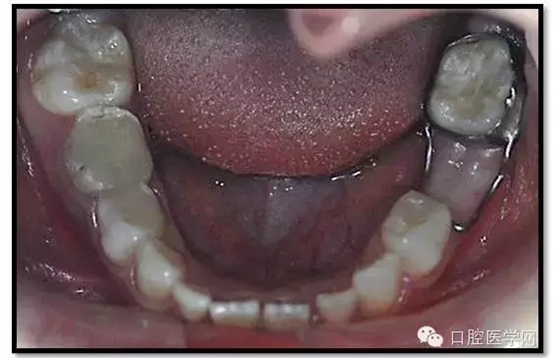

治療結(jié)束后3個月復(fù)查

復(fù)查:無不適

檢查:口腔衛(wèi)生一般,牙面軟垢菌斑中量。 85O、84DO充填完好,邊緣密合,叩(-),不松,齦無紅腫。

75帶環(huán)絲圈式間隙保持器完好,無松動,無咬合不適。

余牙充填體完好密合,未查及繼發(fā)齲和新發(fā)齲壞。

治療結(jié)束后7個月復(fù)查

85O、84DO充填完好,邊緣密合,叩(-),不松,齦無紅腫。X線:84、85根分歧透射影,44、45骨硬板連續(xù),恒牙胚上方骨板厚約2-3mm。75帶環(huán)絲圈式間隙保持器完好,無松動,無咬合不適。64MO中齲。 64MO中齲去腐凈,自酸蝕,SEBOND,樹脂充填。 口腔衛(wèi)生宣教,囑3個月后復(fù)診。